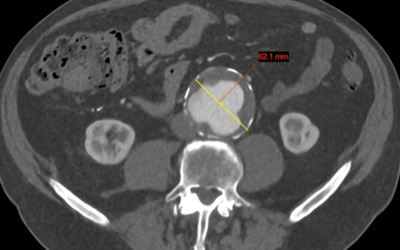

Abdominal Aortic Aneurysm (AAA) Screening

An aneurysm refers to an abnormally wide (dilated) blood vessel. This commonly affects the aorta, the main blood vessel in the tummy and chest. An Abdominal Aortic Aneurysm (AAA) affects around 3% of people over the age of 50. Why is an AAA important? A ruptured AAA...